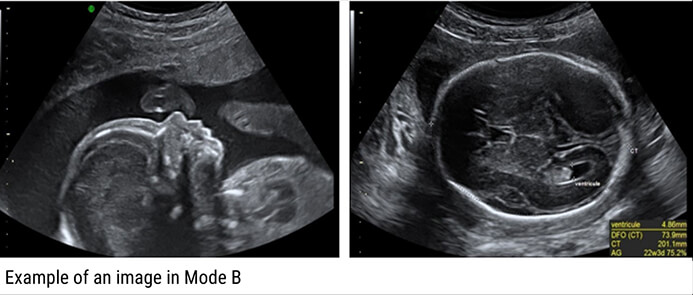

B-Mode

The B-Mode, or Brightness Modulation, is the most common form of ultrasound imaging. It is the display of a 2D map of B-Mode data. The B-Mode is based on the brightness which depends on the intensity of the returning echo. In the B-Mode, there is a Z-axis, which represents the echo intensity or amplitude in function of the depth. The B-Mode will display an image of large and small dots, representing strong and weak echoes respectively.

The amplitude of the echo modulates the gray level of a video monitor. This mode allows the representation of ultrasound data collected in a 2-dimensional image.

Therefore, the solid areas will appear in white, whereas the fluid ones in black.

Examples of Images: The gray levels reflect variations in the texture of the internal organs as shown in these 4 different clinical images.